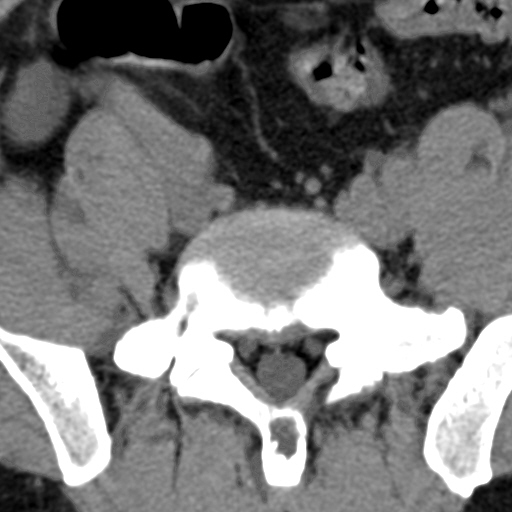

标题: CT4742:椎弓病变,请各位会诊。

男性,37岁,体检发现。

椎弓棘突形态、大小正常,左右椎板及棘突交界区骨质缺损,考虑良性病变(血管瘤可能)。

椎弓棘突形态、大小正常,左右椎板及棘突交界区骨质缺损,边缘清楚,后分见两个小点状高密影,考虑良性病变[血管瘤、成骨细胞瘤,骨纤,骨囊肿]

左右椎板及棘突交界区骨质缺损,周围未见软组织肿块及肿胀,考虑良性病变(血管瘤可能)。

破坏区呈彭胀性 切有硬化缘 考虑良性占位  囊肿可能性大